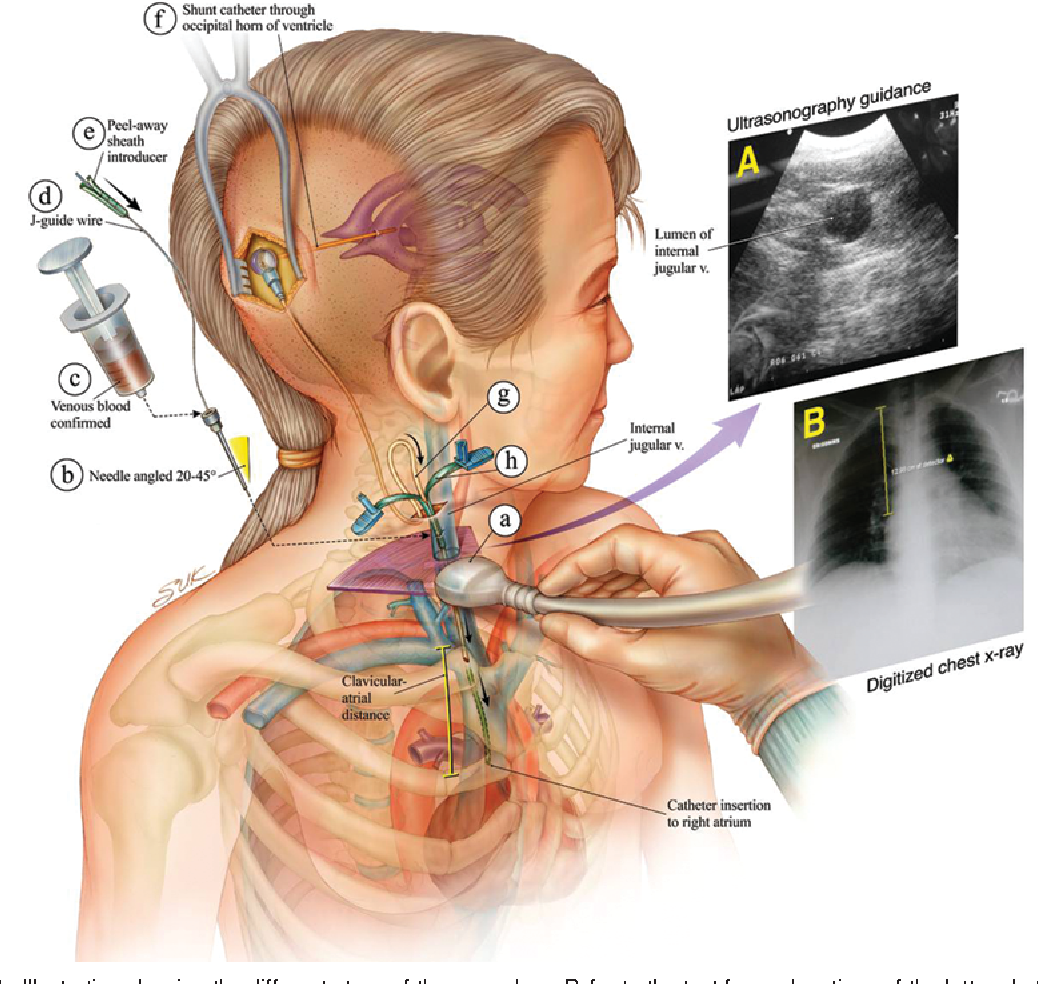

Вентрикуло-перитонеальный шунт: Показания и применение

Раздел: Фотоальбом решений